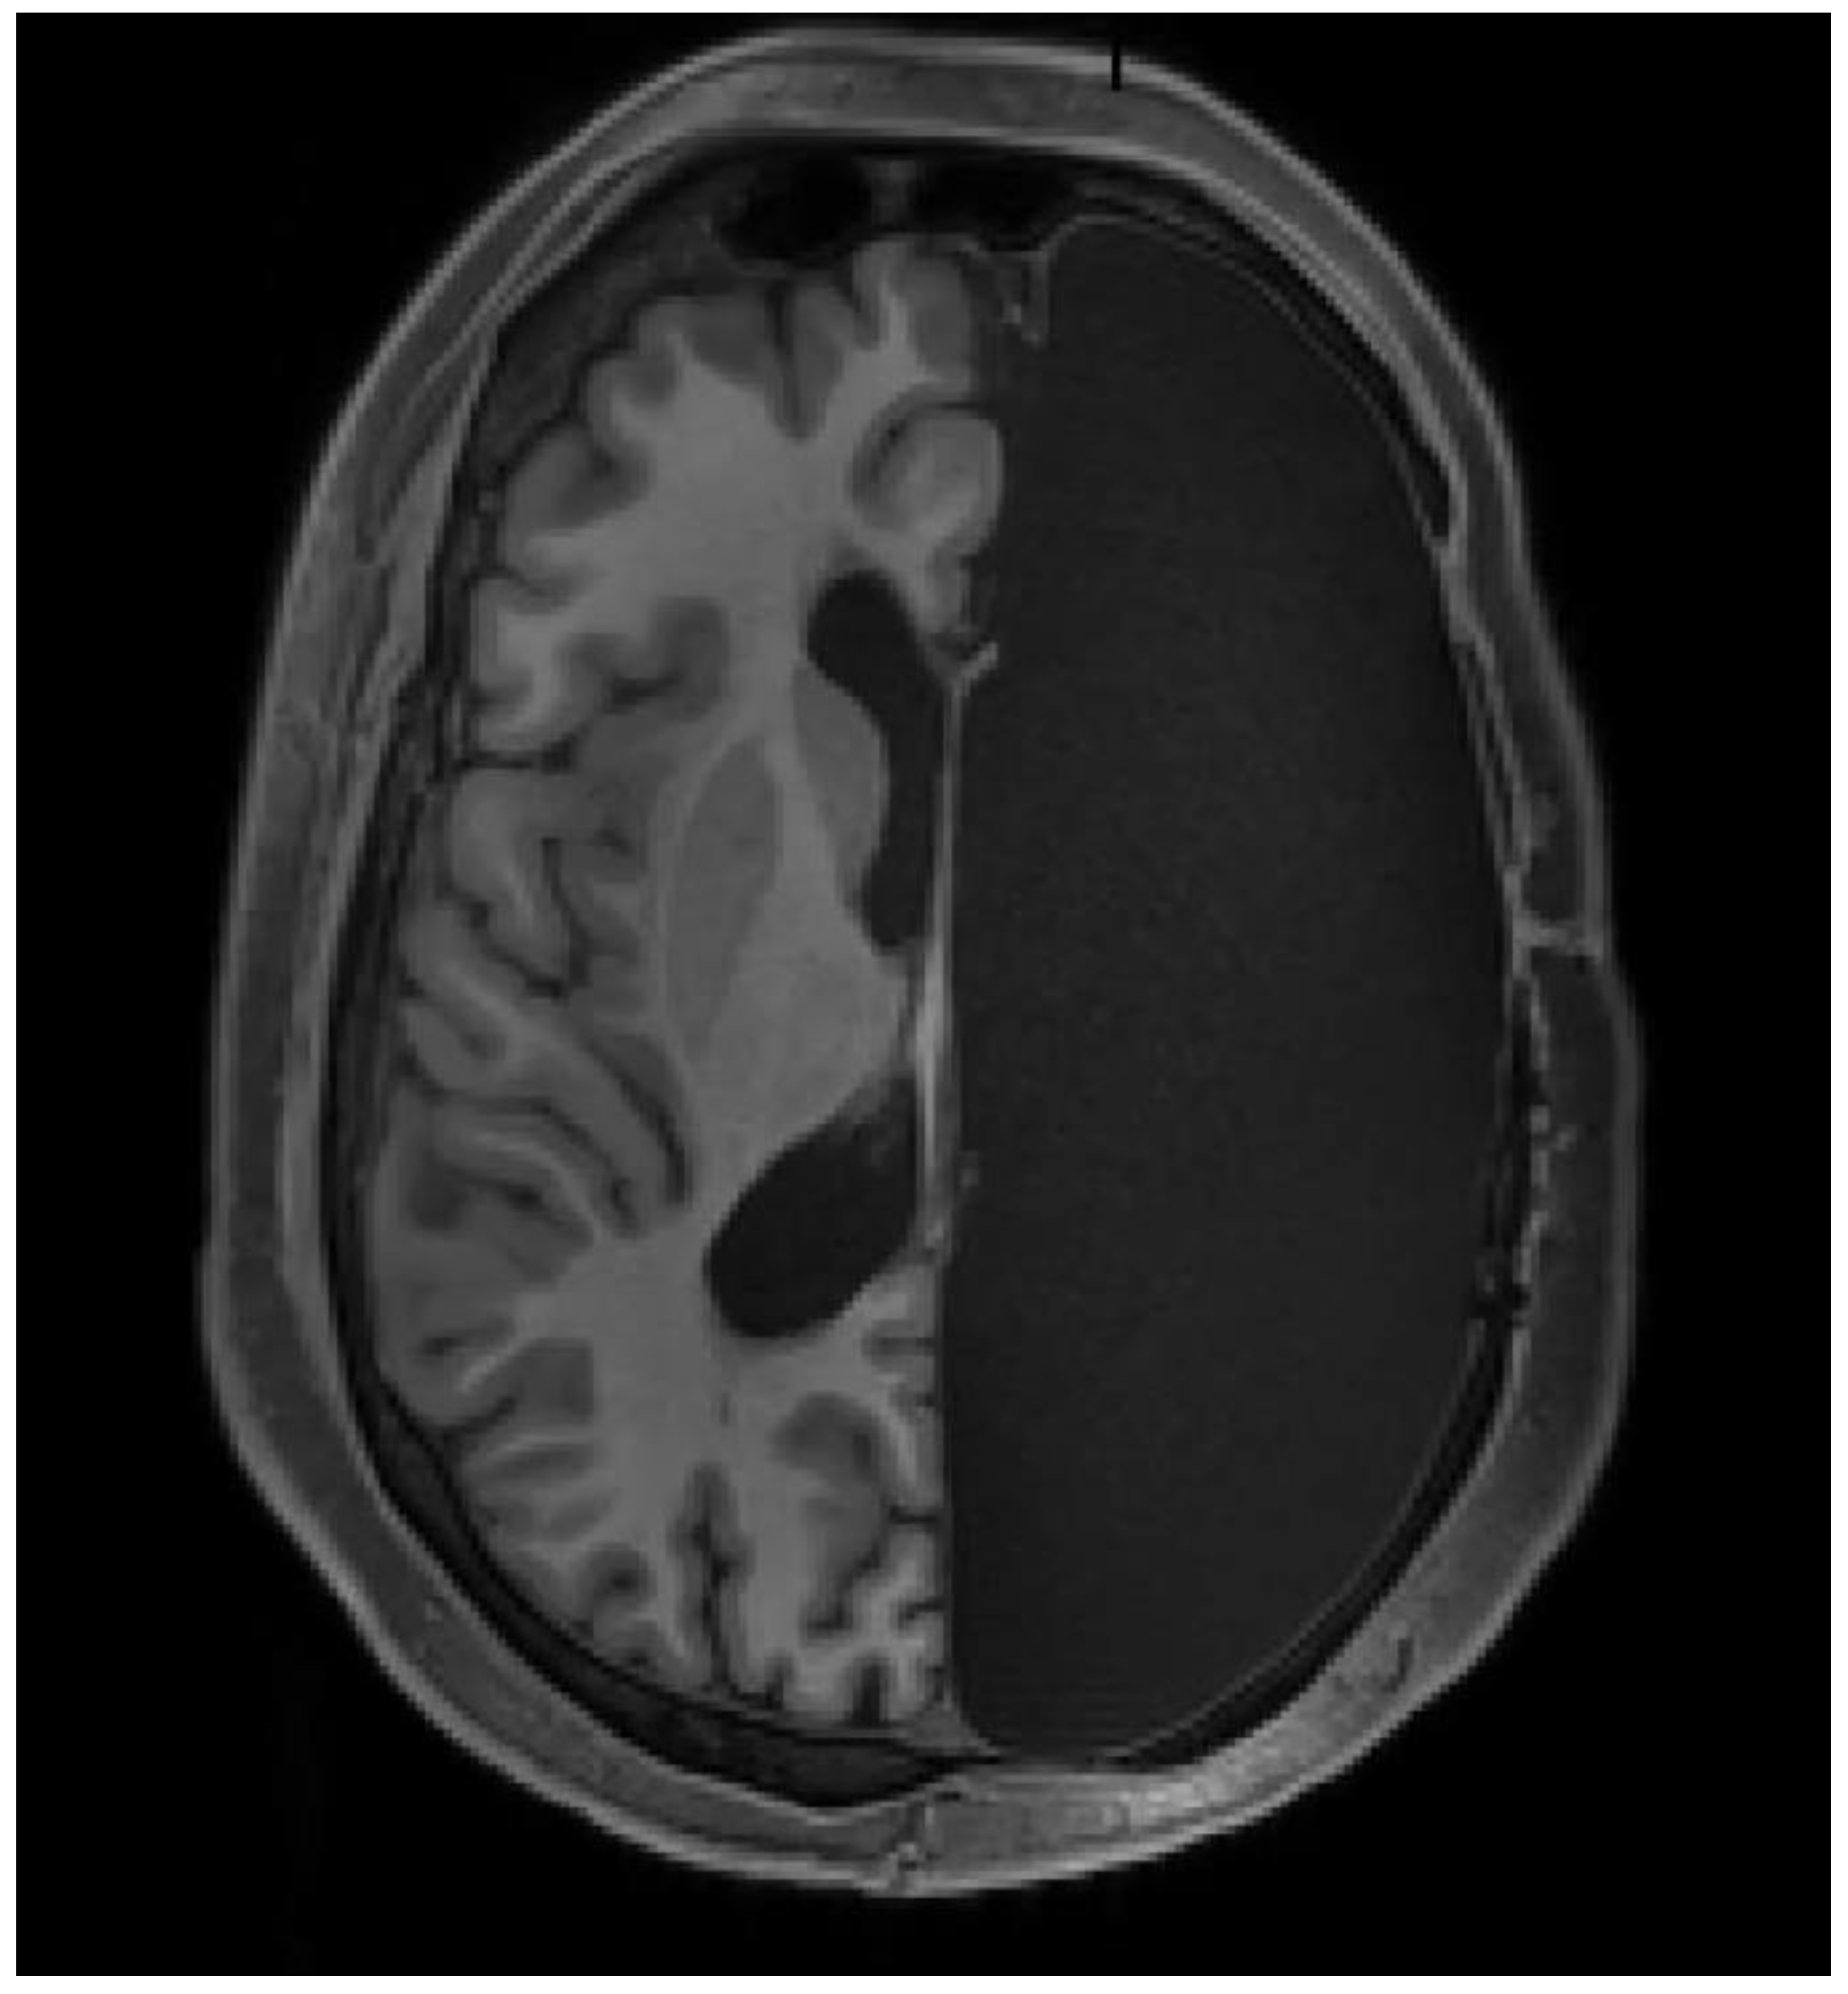

Children in particular demonstrate remarkable plasticity. A hemispherectomy, where half of the brain is removed (figure 8) as a last-resort for treating ailments like epilepsy, is one of the most remarkable instances of this: children who receive a hemispherectomy might recover near-full functionality, indistinguishable from healthy adults (Sheikh, 2019).

Figure 8. An MRI brain scan of an adult who had a hemispherectomy as a child. From: (Sheikh, 2019).

Preprints 119514 g008

In the brains of these individuals we see complete functional rewiring of connections, new regions to pick up the tasks we see in the other hemisphere of healthy adults. There’s often more cross-talk, information sharing, and collaborative decision-making. In essence, the network appears to become more-decentralized, as it no-longer has enough space to specialize and must adapt for decisions shared across regions.